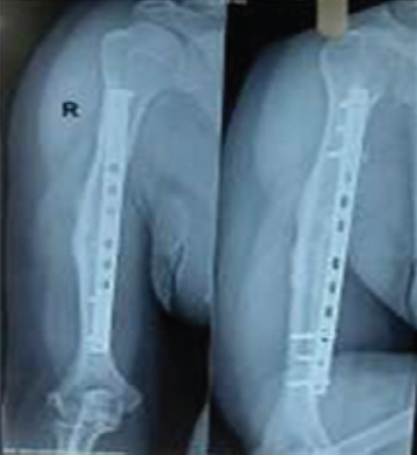

under c-arm guidance. Then distal most screw was inserted. Finally, four more screws – 2 proximal and 2 distal were inserted depending on the access through the surgical incision window. Arm sling pouch was given and elbow range of motion was started immediately, shoulder motion was started at 2 weeks. Case follow-up radiological and clinical images- Figures 5-8. Fluoroscopy shoots are taken frequently during this procedure to confirmed the placement of the plate (equidistant from the fracture and maintain the working length), reduction of the fracture site and screw length.

Figure 5: Anterior bridge plating.10 months postoperative.